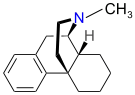

Morphinans

Morphinan series

- Methorphan (racemethorphan)

- N-Methylmorphinan

Structures

| Other morphinans | ||||

N-Methylmorphinan N-Methylmorphinan |

Dextromethorphan Dextromethorphan  levomethorphan levomethorphan |